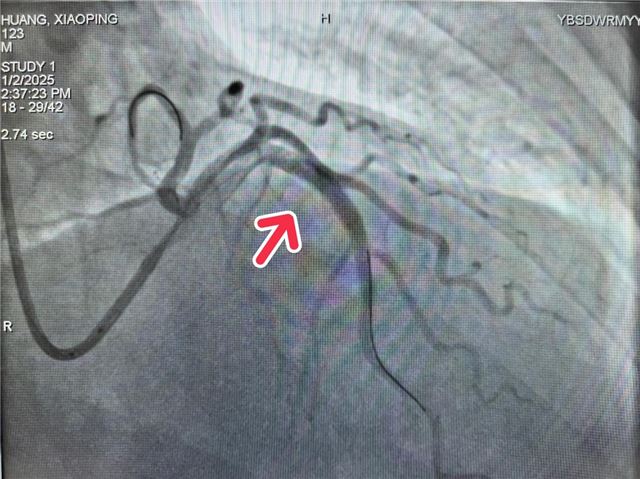

介入室胡前坤主任接到消息后远程指导给予急救药物和抗凝治疗,并提醒警惕恶性心律失常。话音刚落,患者突发抽搐、意识丧失,陷入昏迷状态,监护仪警报响起:室颤!这是心梗最危险的并发症,心跳骤停随时可能发生。介入室、急诊科、老年病科医护人员立即联合施救——心肺复苏、200J电除颤……紧张有序的急救之后,患者意识恢复,初步抢救成功!随后,团队迅速为患者施行急诊介入手术,成功开通闭塞血管,恢复血流,将患者从死亡边缘拉回。